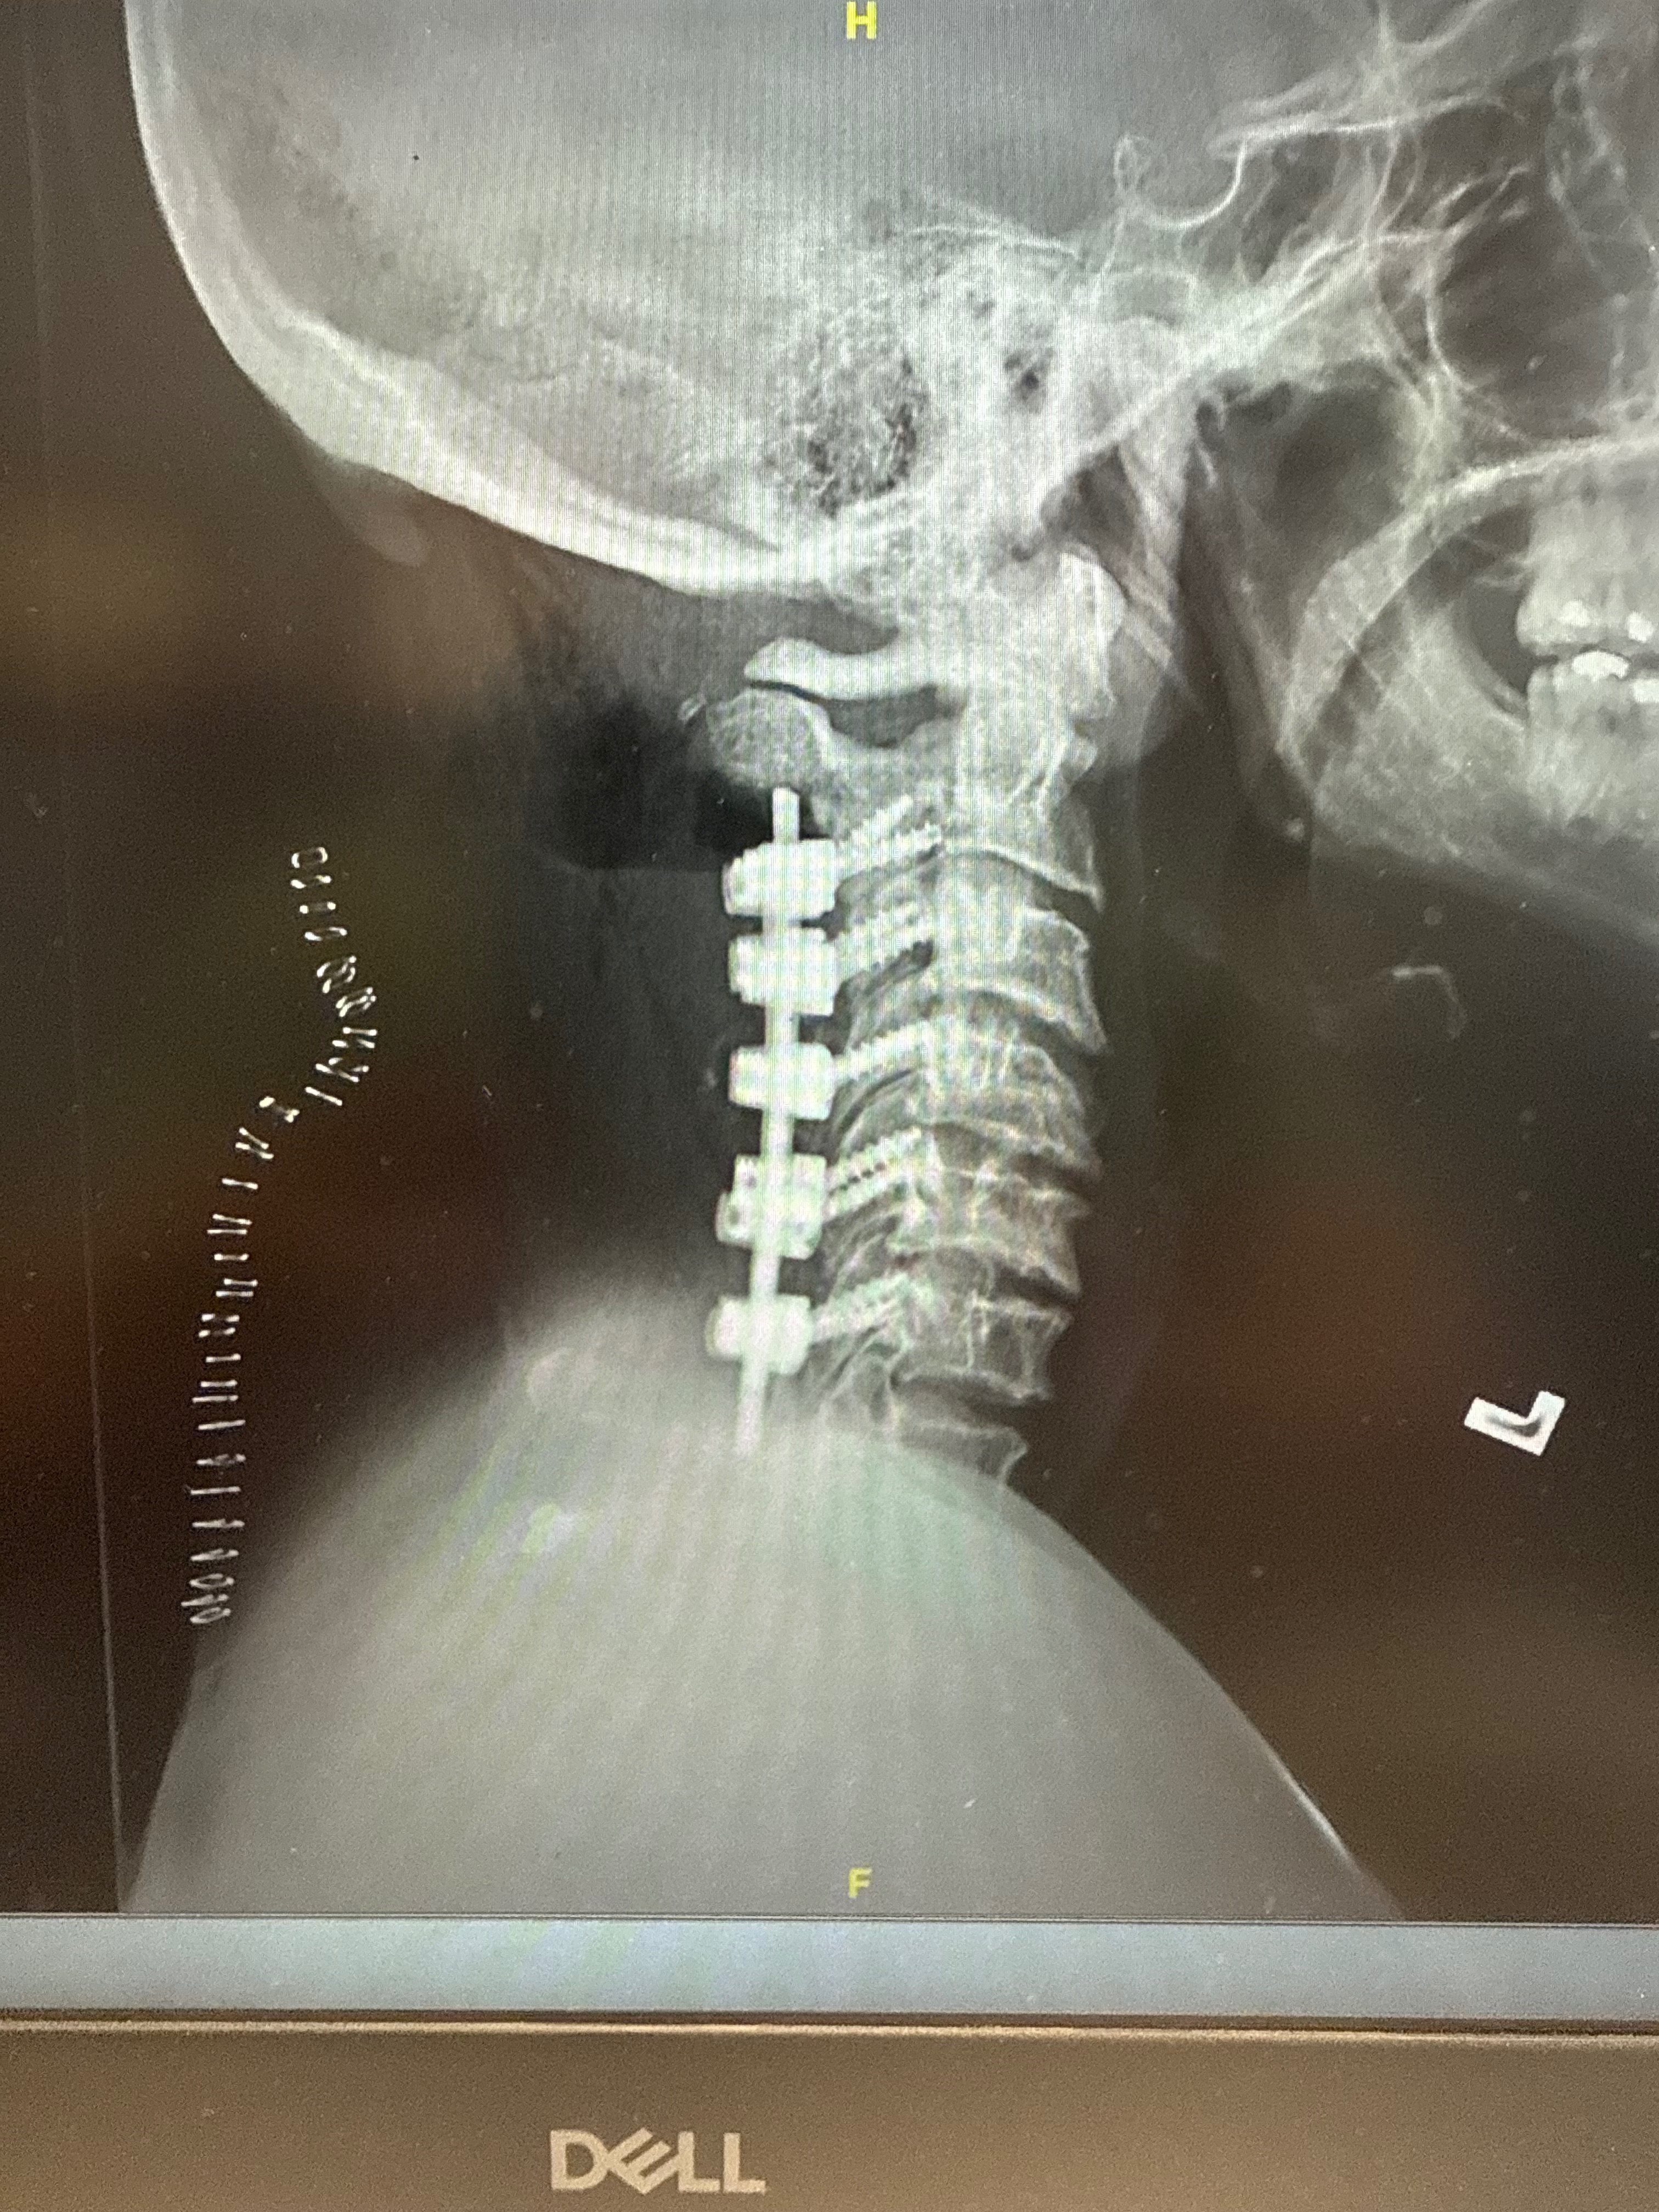

After multiple ER visits and an urgent neurology referral, an MRI revealed moderate to severe spinal stenosis, severe foraminal narrowing causing nerve impingement, and a lesion measuring 5 x 4 x 5 mm between C2–C3, along with bulging discs from C2 through C6.

A neurosurgeon confirmed that the only option was spinal surgery — warning Alicia that while surgery could stop her condition from worsening, she might never regain full function of her hands, and that additional surgeries would likely be needed in the future.

On September 15th, 2025, Alicia underwent a cervical discectomy and fusion from C2 to C6, a major procedure involving her neck and upper spine. Her recovery has been extremely painful and complex — her incision was closed with 40 surgical staples. Just over a week later, on September 23rd, she was rushed back to the operating room for a second emergency surgery to repair a CSF leak, a serious complication from the initial operation.